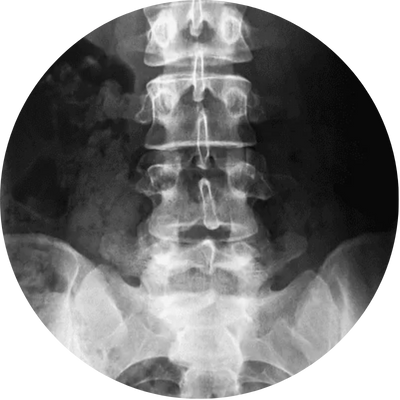

Raio-X da coluna

O raio-x da coluna é um exame de imagem que permite visualizar a estrutura óssea da coluna vertebral. É solicitado para avaliar dores nas costas, problemas posturais, suspeitas de fraturas e deformidades. O que o raio-x da coluna avalia? Vértebras, Espaços intervertebrais, Apófises transversas e espinhosas.